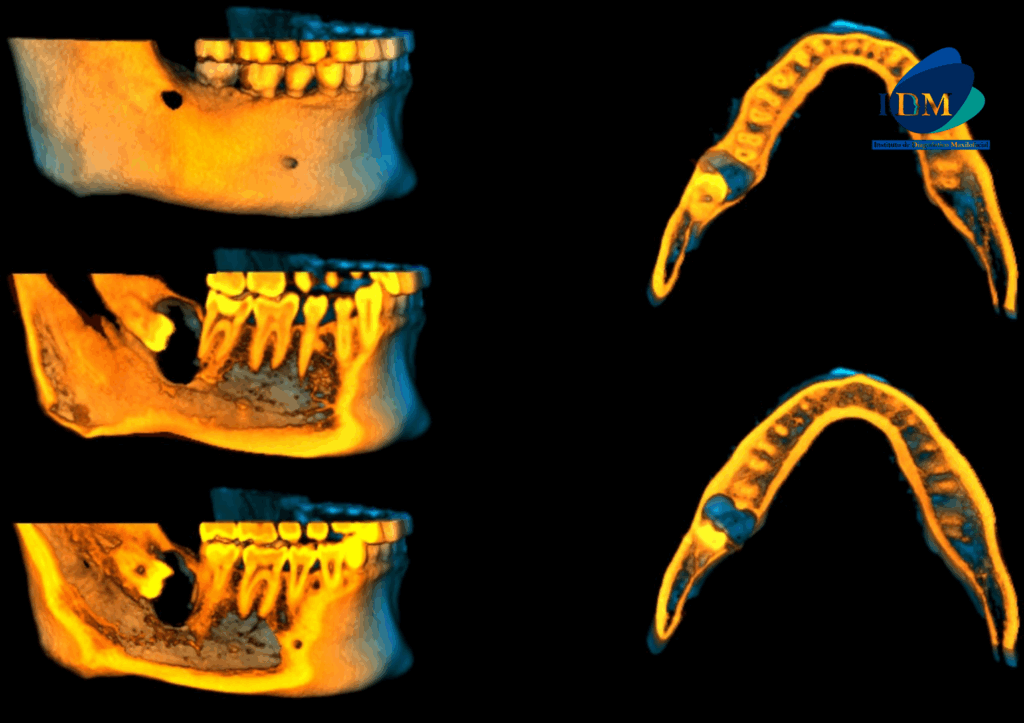

En las reconstrucciones 3D se representa de manera didáctica Quiste Dentigero (Figura 4).

RECONSTRUCCIÓN 3D